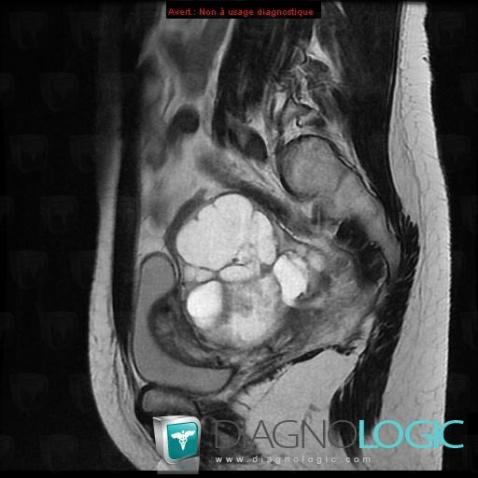

Serous cysteadenocarcinoma, Adnexa / Ovary fallopian tube, Pelvis / Perineum, MRI

- Diagnosis Serous cysteadenocarcinoma (link to Serous ovarian tumor), Location(s) Adnexa / Ovary fallopian tube, with gamuts T2 WI hyperintense adnexal mass, Cystic adnexal massPelvis / Perineum, with gamuts Large pelvic mass, Cystic pelvic mass